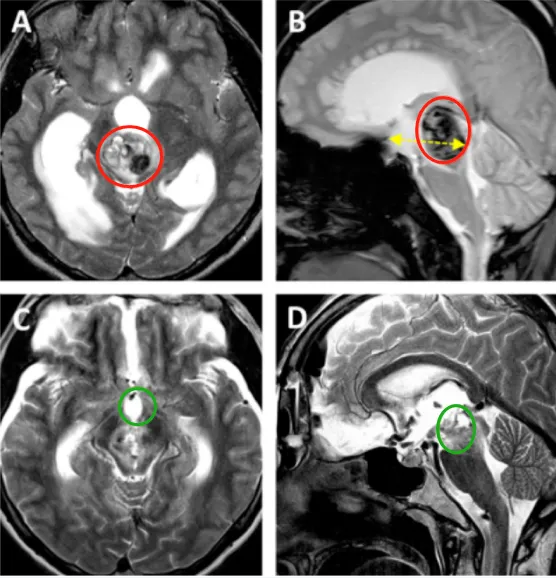

同为延髓肿瘤,走向不同命运的他们 一名21岁的女性,突发头痛,伴有恶心和严重的弹射性呕吐,整整持续了12小时。随着头痛不断加重,在症状出现12小时后入院,随后迅速进展为深度昏迷,...